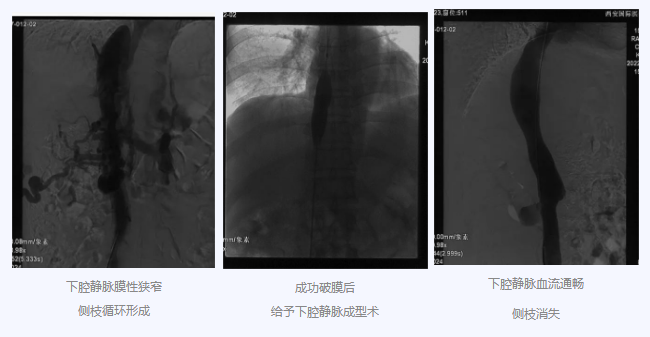

入院后,在韓國宏院長的安排下,臨床經(jīng)驗豐富的醫(yī)師給老謝做了B超、CT 等檢查,結(jié)果顯示:三支肝靜脈近心端閉塞,肝內(nèi)側(cè)枝循環(huán)形成,下腔靜脈近心房入口處隔膜樣狹窄,隨后的DSA血管造影也證實(shí):下腔靜脈狹窄,且有側(cè)枝形成,最終確診困擾老謝20年的疾病為混合型布加綜合征,是一種罕見病。

明確診斷后,韓院長帶領(lǐng)團(tuán)隊縝密分析老謝的病情,為其制定最佳的治療方案,考慮到老謝的根本病因是下腔靜脈阻塞,介入手術(shù)成為首選治療方法,通過微創(chuàng)介入手術(shù),可準(zhǔn)確打通患者的閉塞血管,癥狀迅速緩解。做好充分術(shù)前準(zhǔn)備后,為患者行“下腔靜脈成型術(shù)”,精準(zhǔn)定位快速貫通,閉塞的下腔靜脈順利開通,手術(shù)圓滿完成。